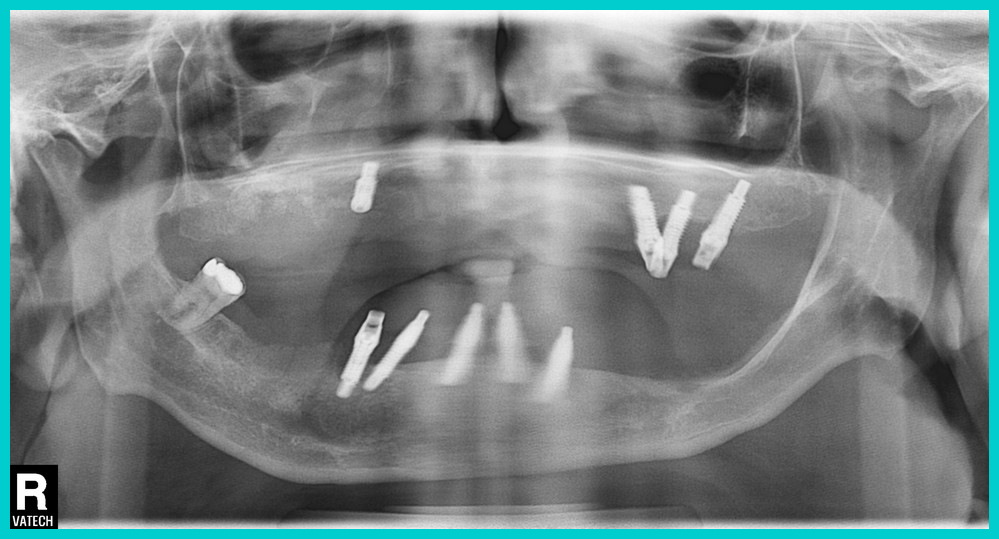

View attachment 299113